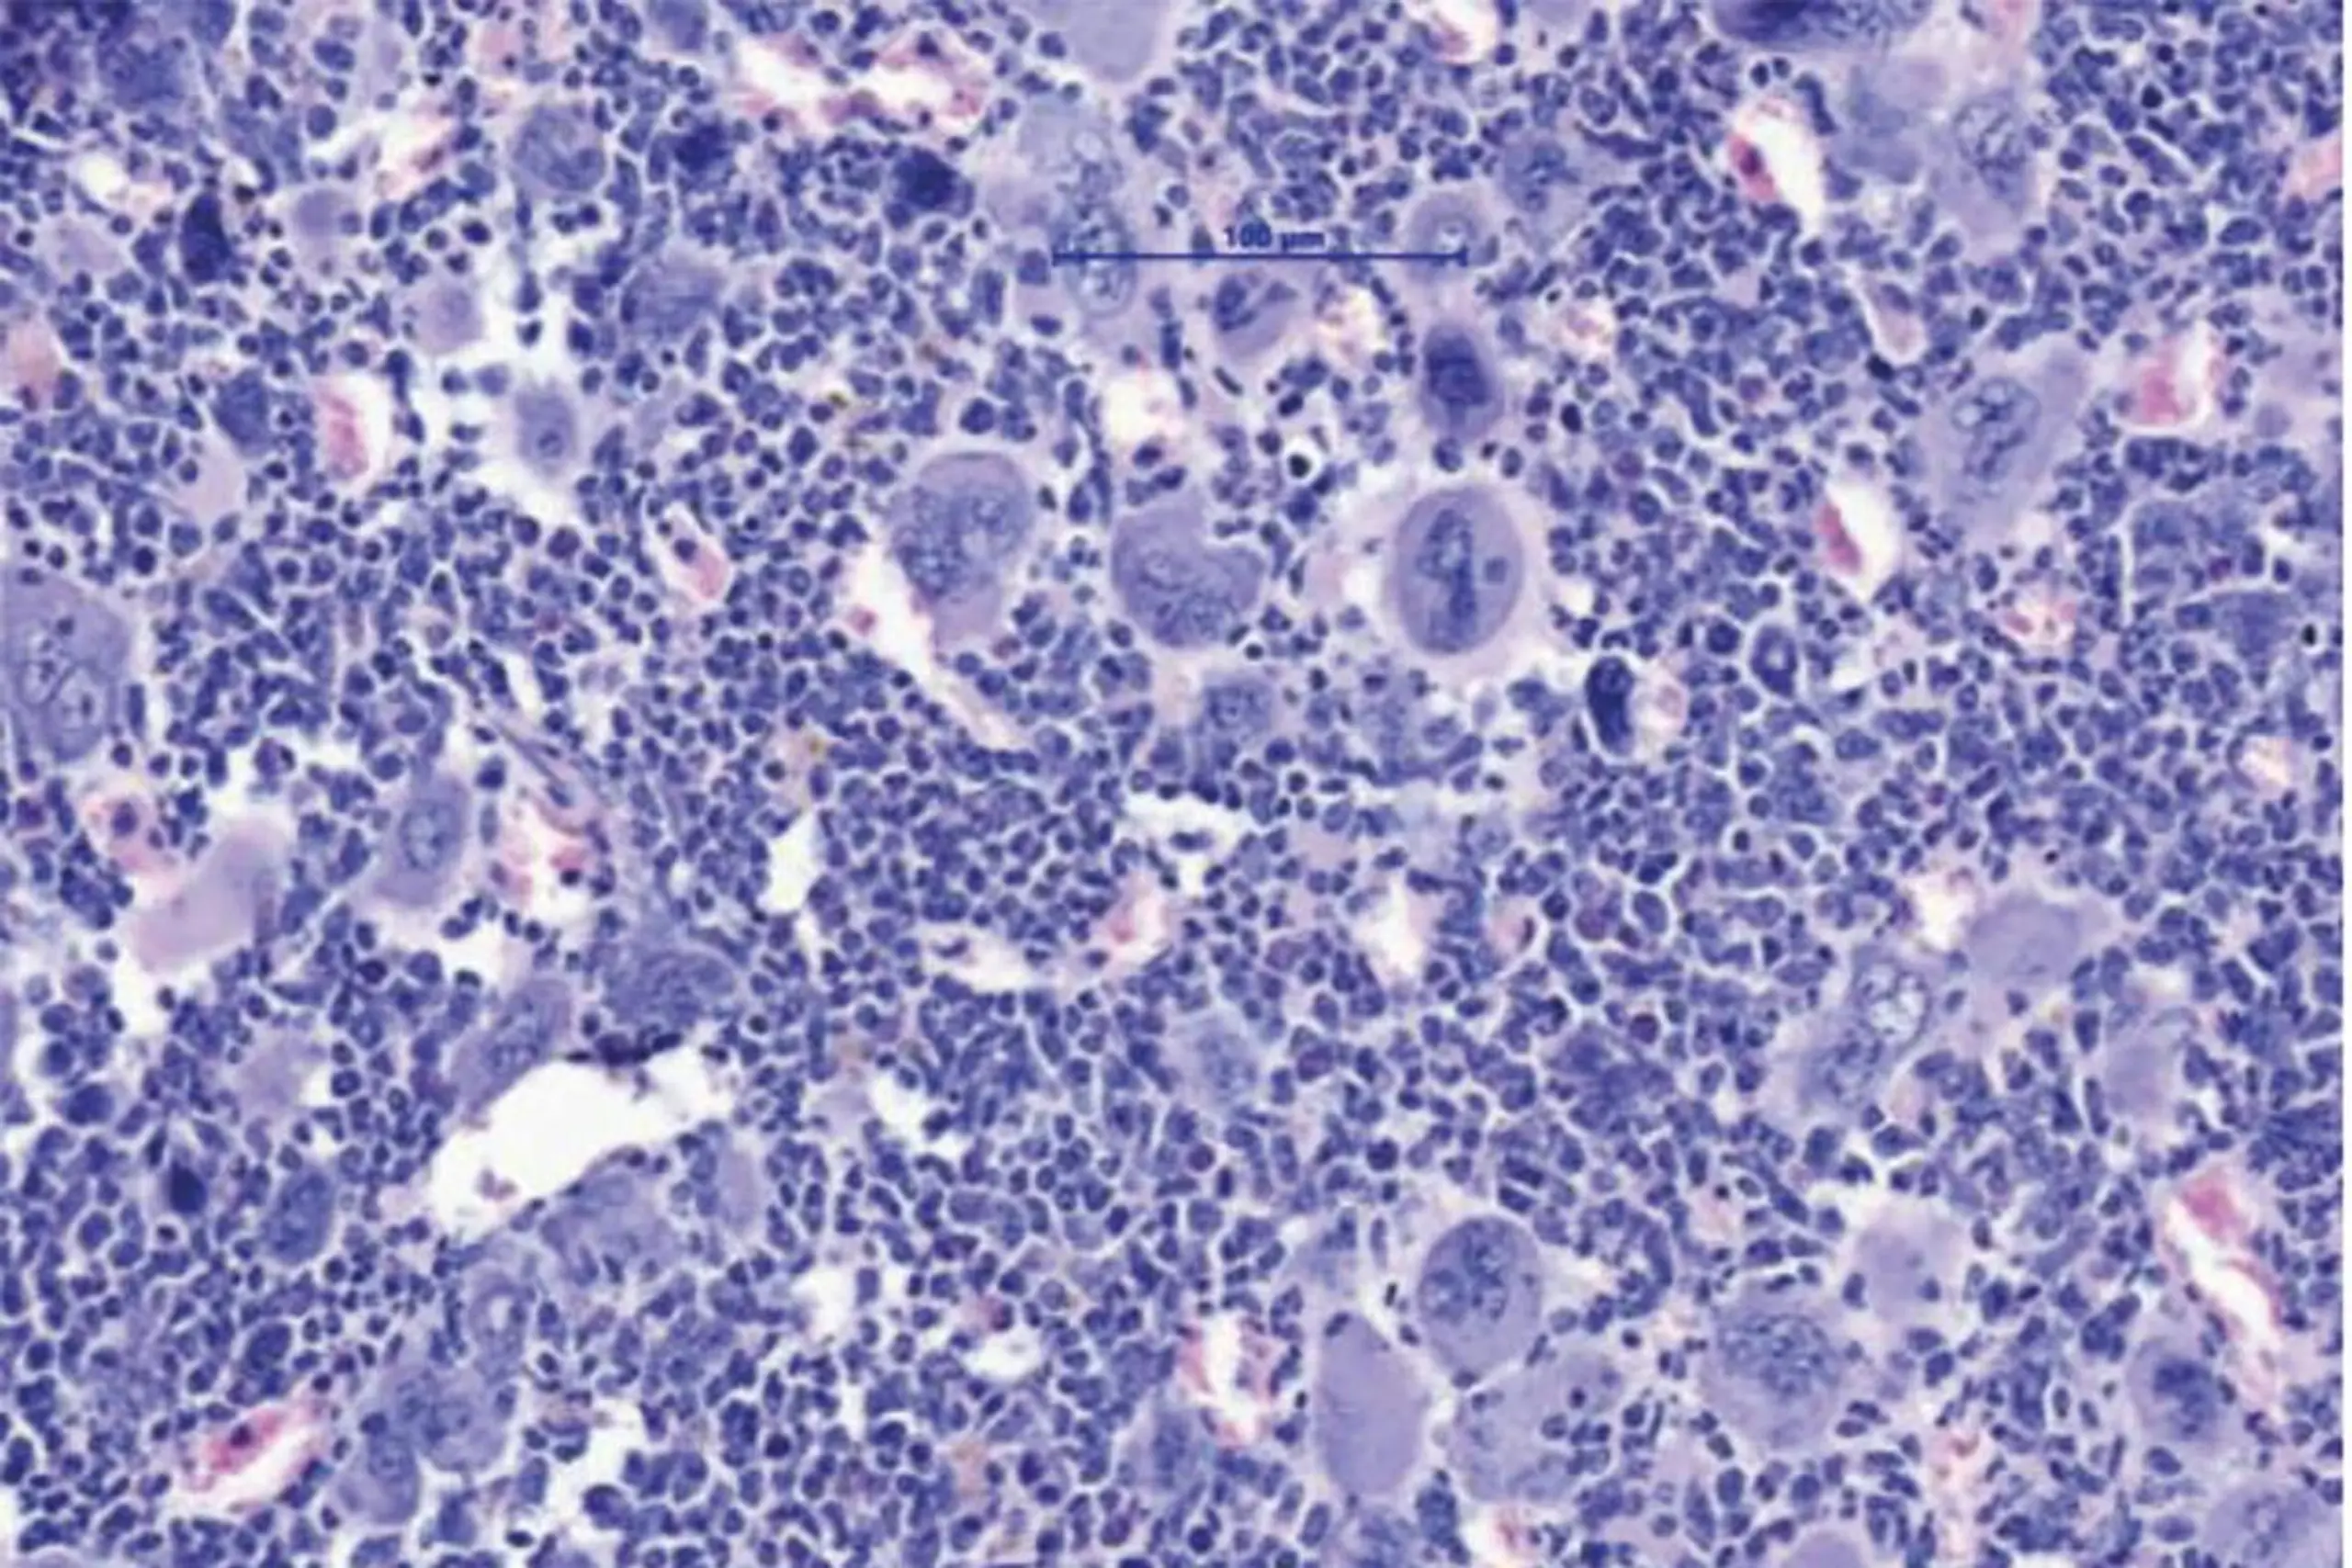

Myeloproliferative Neoplasien, eine Gruppe von Blut- bzw. Knochenmarkerkrankungen, sind durch eine Überproduktion von Blutzellen gekennzeichnet, treten in der Regel ab einem Alter von etwa 60 Jahren auf und können über Jahre kontrolliert verlaufen, bevor es zu einer lebensbedrohlichen Vernarbung des Knochenmarks (Myelofibrose) und in manchen Fällen zur akuten Leukämie kommt. Ausgelöst werden die Entzündungsprozesse unter anderem durch die Treibermutation JAK2V617F, die sowohl bösartige als auch begleitende sowie noch gesunde Blutzellen betrifft.

INNSBRUCK - ÖSTERREICH: FOTO: APA/MUI/Univ-Klinik für Innere Medizin V